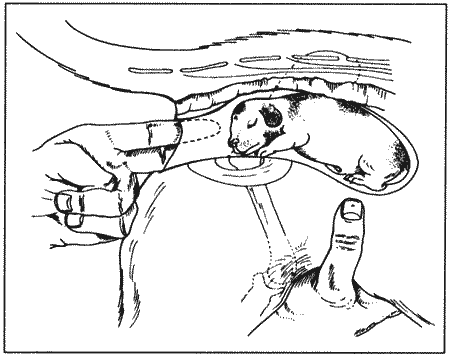

Вагинальная эндоскопия

Прекращение секреции эстрадиола фолликулами и переход их к секреции прогестерона приводят к снижению как отечности, так и васкуляризации слизистых оболочек, что сопровождается выраженным изменением характера вагинальных выделений, выявляемым с помощью вагинальной эндоскопии. На стадии проэструса слизистая оболочка становится более выпуклой и отечной, затем наблюдается ее уменьшение; по мере приближения овуляторного пика слизистая сжимается и бледнеет, в некоторых случаях становясь практически белой (фиг. 1.1). Перечисленные изменения свидетельствуют о приближении стадии, характеризующейся постепенным повышением концентрации прогестерона перед овуляцией и последующим наступлением фертильного периода. Эти изменения легко узнать, имея даже небольшую практику (фиг. 1.3), кроме того, они настолько воспроизводимы, что по набору признаков их можно оценивать полуколичественно. Вагинальная эндоскопия весьма полезна в определении оптимальных сроков вязки. По окончании фертильного периода, т. е. в начале метэструса — слизистая оболочка влагалища бледнеет и истончается, складки становятся закругленными — и что, вероятно, является наиболее характерным признаком, — слизистая в переднем отделе влагалища выглядит раздраженной и при прикосновении быстро сжимается, образуя розетку.

Фиг. 1.3.

Эндоскопическое исследование слизистой влагалища. Динамика изменений на протяжении цикла: (а) проэтрус — розовая окраска и отечность; (b) начало эструса — слизистая бледнеет, отек начинает уменьшаться (обычно перед пиком ЛГ); (c) середина эструса — слизистая бледная, уменьшение отека (сморщивание) явно выражено, что соответствует середине фертильного периода; (d) начало метэструса — видны закругленные складки, при прикосновении слизистая смыкается, образуя розетку (е) (см. Приложение)